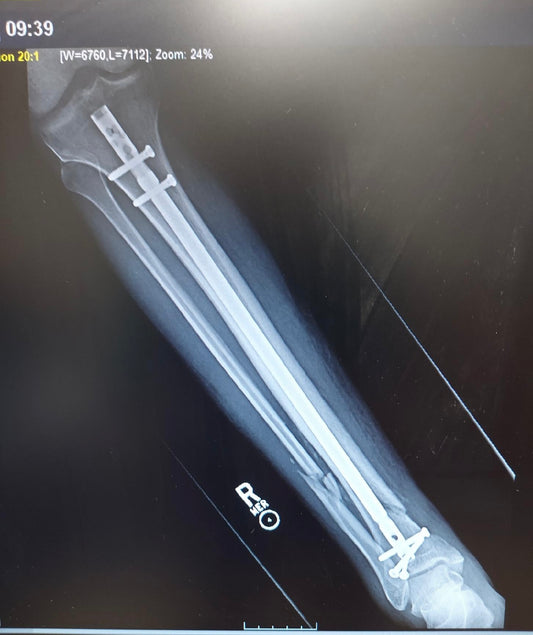

A few weeks ago my brother had an accident while riding his scooter. We’re thankful he is OK, but he did break both leg bones completely through. He has since...